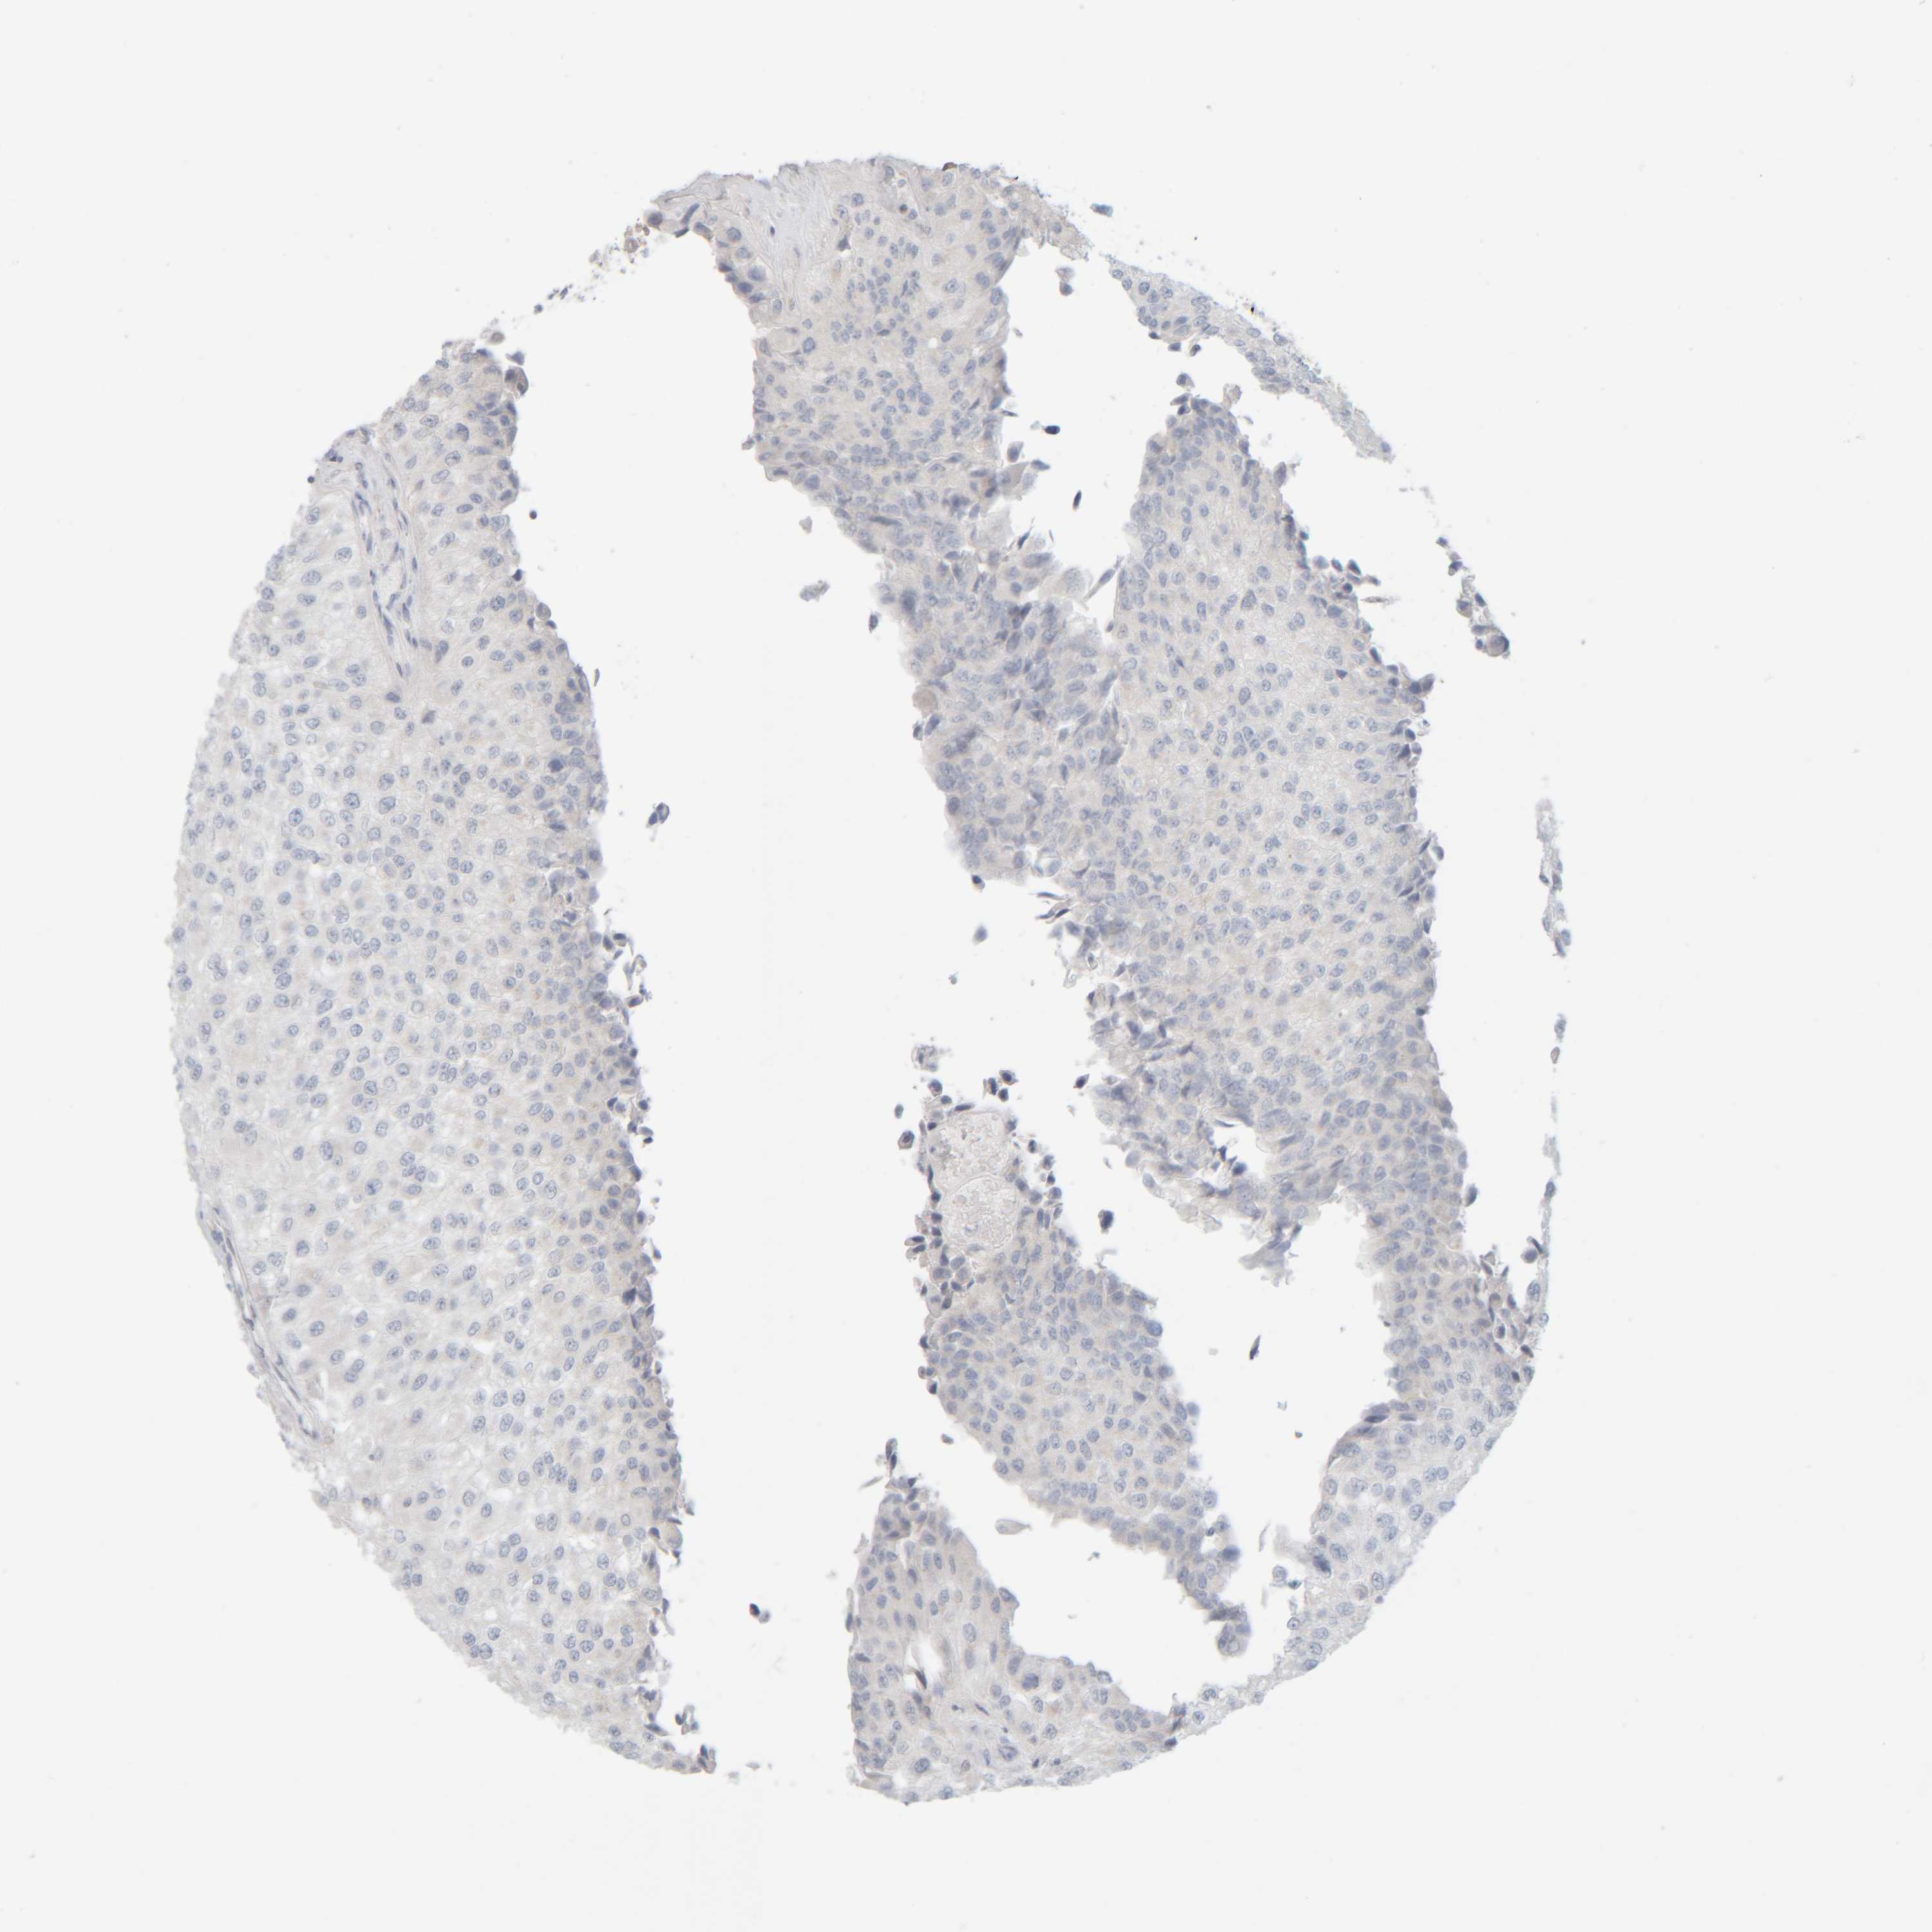

UROTHELIAL CANCER - Protein expressioni

A mouse-over function shows sample information and annotation data. Click on an image to view it in a full screen mode. Samples can be filtered based on level of antibody staining by selecting one or several of the following categories: high, medium, low and not detected. The assay and annotation is described here.

Note that samples used for immunohistochemistry by the Human Protein Atlas do not correspond to samples in the TCGA dataset.

Antibody stainingi

Antibody staining in the annotated cell types in the current human tissue is reported as not detected, low, medium, or high, based on conventional immunohistochemistry profiling in selected tissues. This score is based on the combination of the staining intensity and fraction of stained cells.

Each image is clickable and will lead to virtual microscopy that enables deeper exploration of all samples and also displays staining intensity scores, fraction scores and subcellular localization as well as patient and tissue information for each sample.

Antibody HPA022856

Antibody HPA023489

Urothelial carcinoma, Low grade

Urothelial carcinoma, High grade